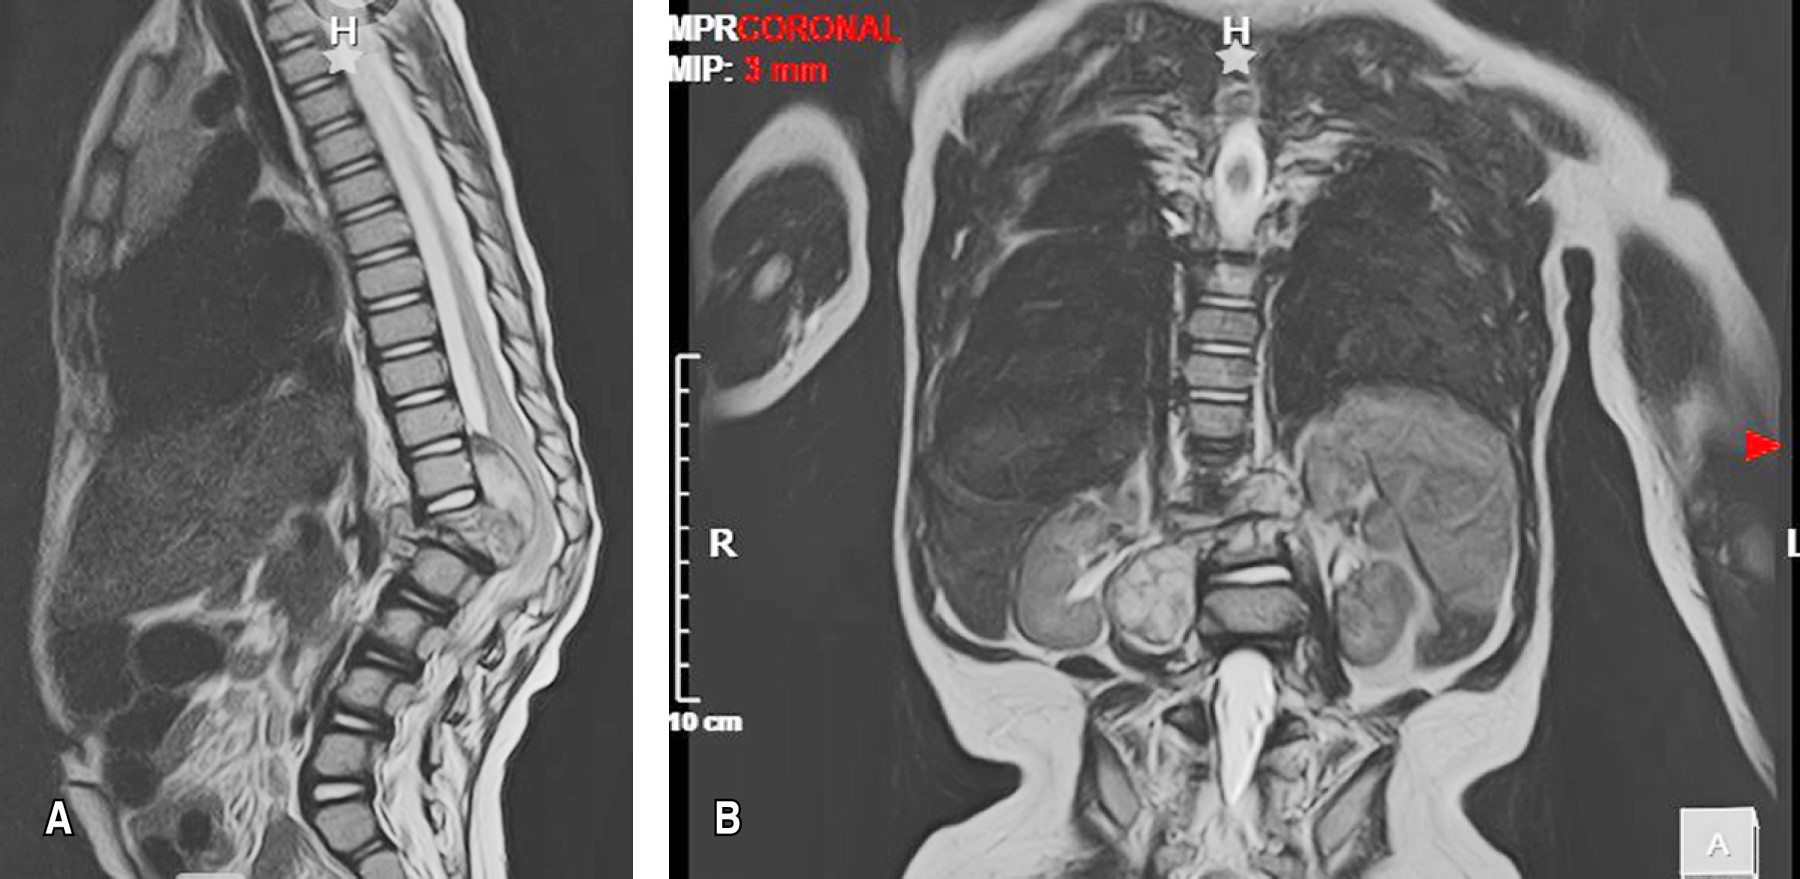

Se reportó una pérdida de peso de 2 kg en un corto periodo de tiempo, lo cual generó preocupación por un proceso infeccioso o inflamatorio subyacente. Se realiza estudio de resonancia magnética nuclear de columna dorsolumbar contrastada (Figura 2), en la cual se muestra síndrome de destrucción vertebral con fractura patológica de las vértebras T12 y L1, erosión en cuerpo vertebral de L1, así como presencia de masa de tejidos blandos hiperintensa con involucro de cuerpo anterior y posterior que formaba una colección (37 × 50 × 47 mm) de aspecto subdural, con contacto de elementos neurales y, al administrar contraste, con realce de la pared con un centro hipointenso. También se solicitó una tomografía axial computarizada de columna dorsolumbar, donde se encontró consolidación pulmonar en la región parahiliar derecha (2.6 × 2.1 cm), junto con adenomegalias cervicales y mediastinales.

Ante la pobre mejoría clínica con el tratamiento conservador durante dos meses, se realizan rayos X (Figura 3) y resonancia magnética nuclear de control (Figura 4), donde se identificó permanencia del colapso vertebral, compresión de elementos neurales y extensión de la colección hacia la región prevertebral y los músculos iliopsoas bilaterales, con cambios en la intensidad de señal a nivel medular sugestivos de mielopatía en el área afectada. Se realiza intervención quirúrgica mediante instrumentación posterior toracolumbar de T12 a L3, hemilaminectomía izquierda en T12-L1 y drenaje de abscesos con obtención de 3 cc de líquido de aspecto purulento en el espacio T12-L1 y alrededor de 8 cc en la región del psoas derecho (Figura 5 y 6).